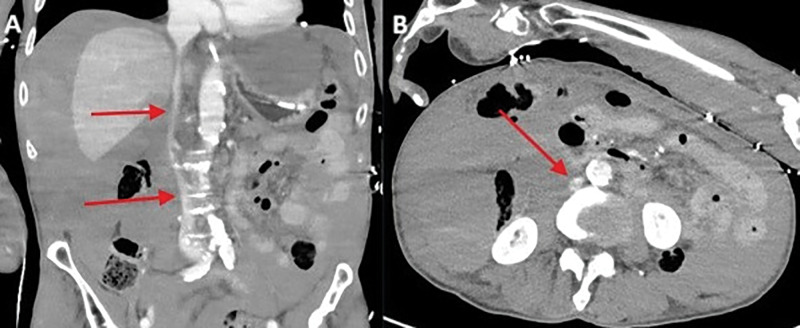

Teaching point: Laceration of the left hepatic vein is a rare but potentially fatal complication of cardiopulmonary resuscitation (CPR) and should be considered in patients with unexplained hemodynamic instability following resuscitation.

Abstract Image